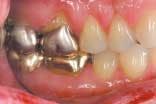

Laboratory communication

Laboratory communication is perhaps the most important part of digital camera ownership. Traditionally, we have taken images of patients' teeth to communicate to our laboratory the shade and texture of the teeth for an indirect restoration. This is still a great application for digital cameras. The advantages of using a digital medium include the following:

Taking images of every indirect restoration will become routine. There is no reason not to take an image of every restoration. Laboratory technicians often are given only a set of stone models on which to build your restoration. When they have an image to go by, the quality of the restoration will be improved immeasurably. Patients will perceive that you are a high tech fastidious dentist who is going to give them a superior product.